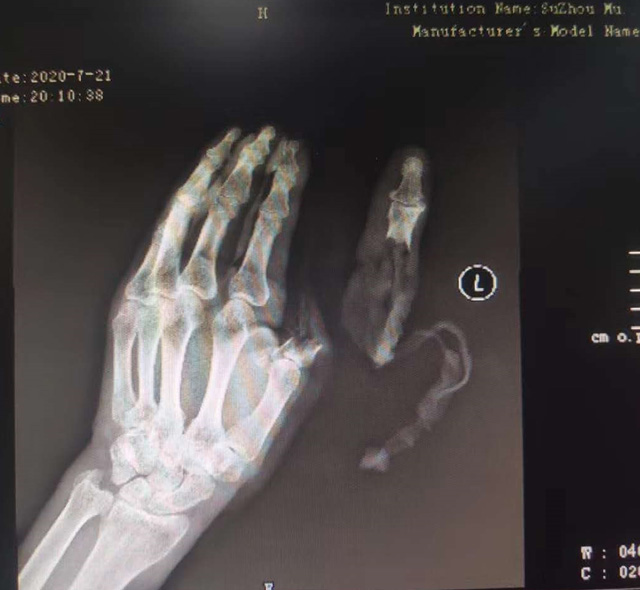

現(xiàn)代快報記者了解到,7月21日下午,這名76歲的老人在家擦拭面粉機時,忘記關閉電源,結果抹布被纏進機器,順帶著將老人的手也帶進機器中。老人奮力掙脫,可為時已晚,待將手取出時,已經(jīng)血肉模糊,大拇指在脫落后還被絞入機器軋了一圈……

△老人送醫(yī)時的手部狀態(tài) 蘇州市立醫(yī)院供圖

拇指可以影響一只手40%的功能,為此醫(yī)院立即制定了手術方案,決定為老人進行斷指再植術,盡力為其保住拇指。由于該患者年紀大、血管彈性差,動脈血管分層也很嚴重,面對重重困難,醫(yī)生在顯微鏡的輔助下,小心翼翼地將血管、神經(jīng)重新吻合,并修復肌腱、皮膚。經(jīng)過5個多小時努力,最終再植成功。

經(jīng)過和患者反復溝通,醫(yī)生決定為老人選擇腹部帶蒂皮瓣手術。即先將發(fā)黑壞死的皮膚清除,再將腹部皮膚覆蓋在手部皮膚缺損處。8月24日,醫(yī)生在老人右下腹設計了一個皮瓣,將老伯的左手拇指用皮瓣覆蓋。經(jīng)過3周的精心護理,斷指成功“復活”。9月14日,醫(yī)生將皮瓣蒂部斷開,此時,皮瓣和拇指重新建立了可靠的血運,不僅拇指保住了,長度也和以前的一樣。